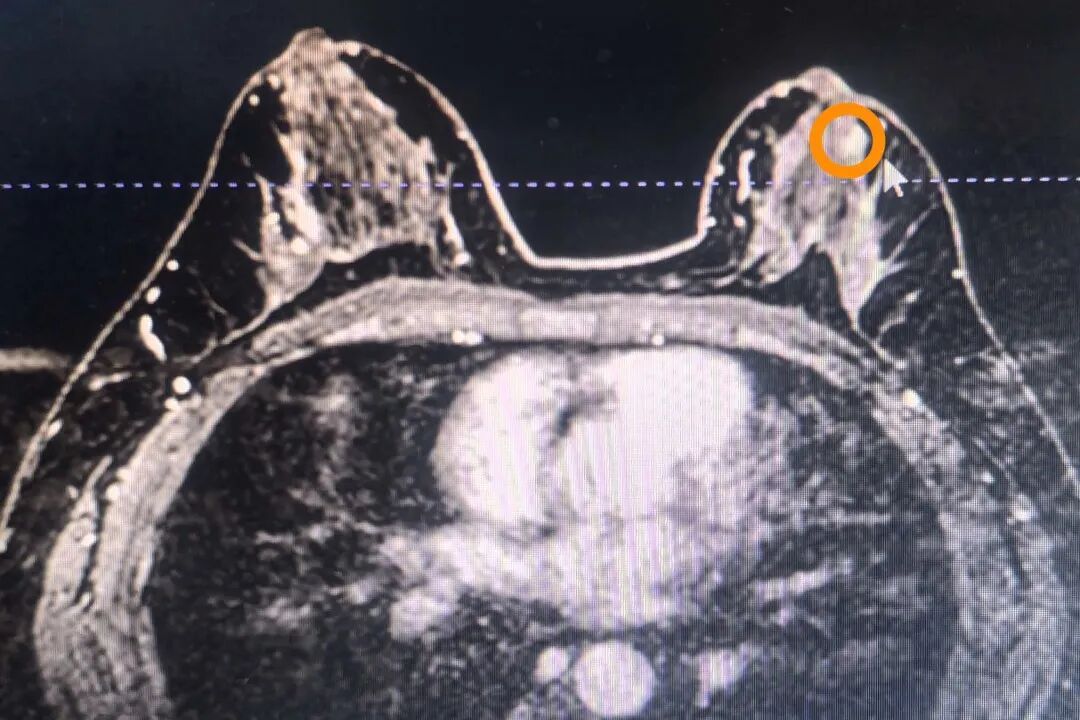

乳腺核磁檢查, 左乳2-3點(diǎn)鐘方向非腫塊樣病變, 左乳4點(diǎn)方向非腫塊樣病變,內(nèi)部強(qiáng)化不均勻,邊緣少許毛刺。